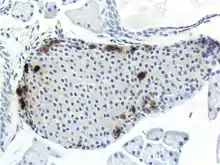

Mouse islet immunostained for pancreatic polypeptide

Mouse islet immunostained for insulin

Mouse islet immunostained for glucagon